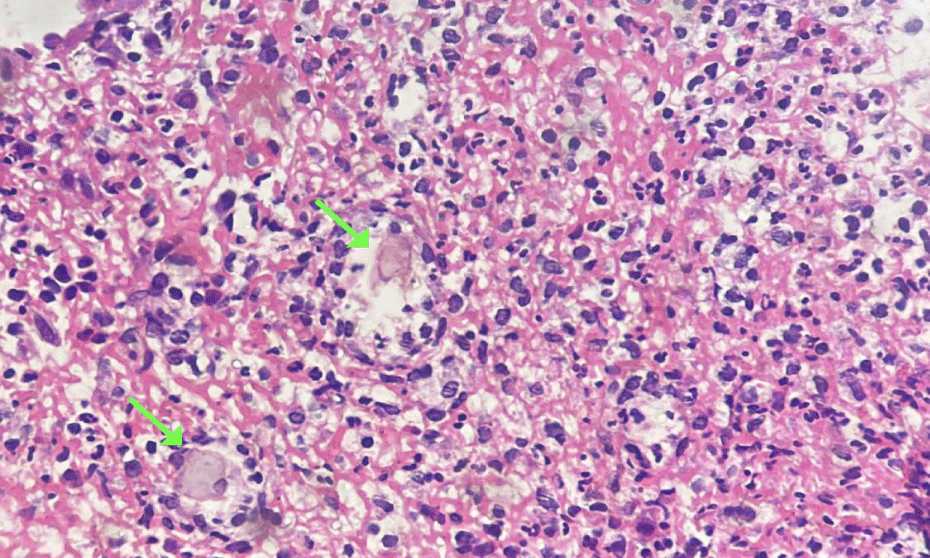

A 39-year-old man, post kidney transplant for focal segmental glomerulosclerosis, and on daily hemodialysis, presented to the emergency department with syncope and significant hematochezia, with hypotension and a drop in 3g/dL of hemoglobin levels. He was under treatment with sevelamer hydrochloride, calcium carbonate, acetylsalicylic acid, clopidogrel and vitamin D. Haemorrhagic shock was treated with blood transfusions and norepinephrine. Diagnostic tests showed no infectious pathogens, and EGD revealed mild gastritis. Despite the interruption of vasoactive drugs and blood transfusions, persistent hematochezia led to a colonoscopy, which revealed a cecum with multiple ulcers and friability (Figure 1), leading to suspicion of Crohn's disease. A histopathological analysis showed crystalline material under microscopy, suggestive of colitis associated with sevelamer (Figure 2). Discontinuation of sevelamer resulted in the cessation of bleeding and stabilization of his condition.